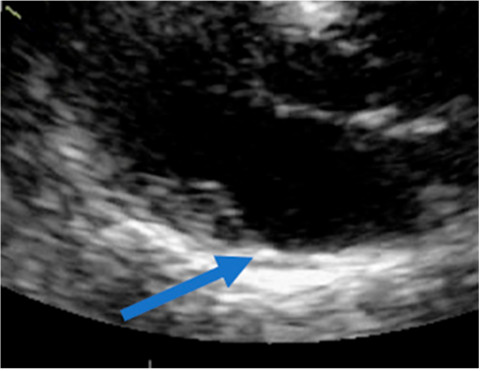

Ahora, la imagen diastólica de este mismo paciente (Figura 5): se observa claramente que la inserción de la mitral esta separada de la unión auriculoventricular, lo que demuestra que sí es posible ver la disyunción del anillo en diástole

La disyunción real, en la que es posible observar la inserción anormal en diástole como en el paciente de la figura 5 (esquemas C y D de la Figura 6)